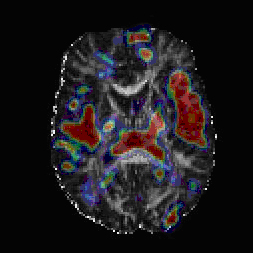

Composite diffusion tensor imaging scan image shows areas (red and to a lesser extent blue) where white matter fiber tracts and surrounding tissue differed between schizophrenia patients and controls.

Source: Ragini Verma, Ph.D., University of Pennsylvania, Department of Radiology-->